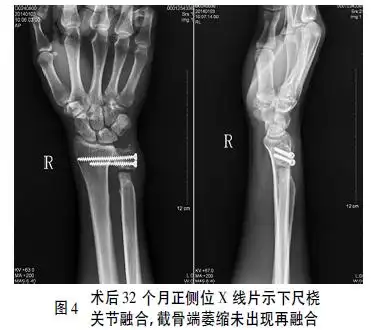

少见下尺桡关节掌侧脱位二例

sauvékapandji术治疗陈旧性下尺桡关节掌侧脱位1例报告并文献复习